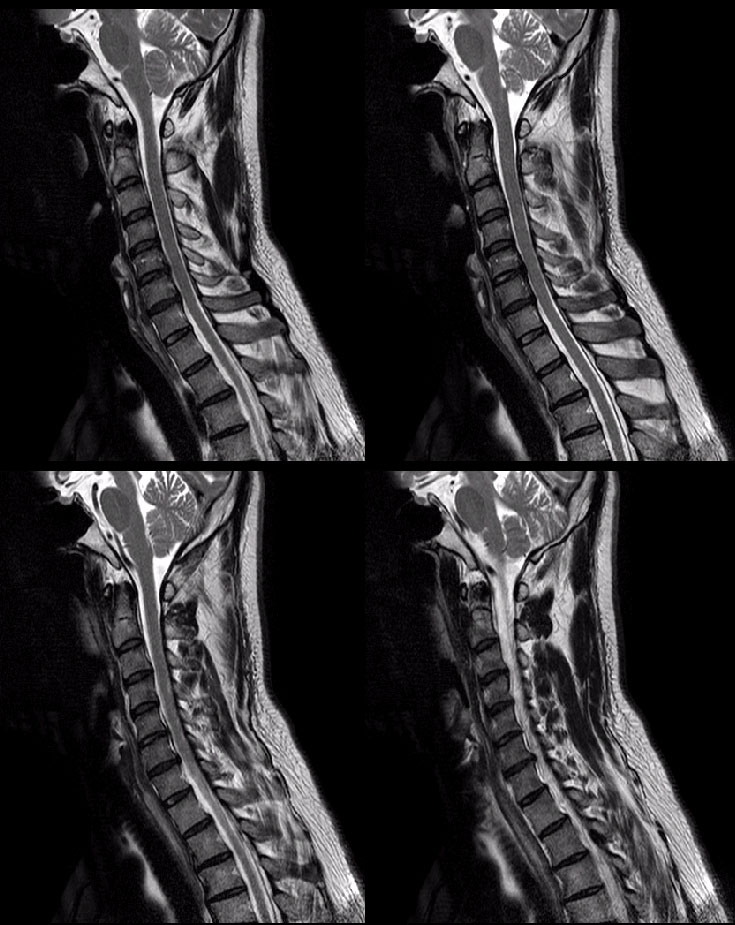

177 81 47 ˰Ե ƴ ͳ ī䳪 α õ ش 6C. κ 6C.ھ Ḳ 6C.ٸħ 7C.Ȳġ 7C. 1T. κ 2T. Ʒκ 9T.˷ ()ũ( ߰Ż) ڸ(߹) Ը ũ(߰Ż)ġ, , Ḳ ġ ϰ Ѱ Ḳ, Ȳġ κа Ʒκ 2 ӵǰ . ǿ ġḦ ް ȣ . MRIԿ 5,6 6,7 ְ ణ . |